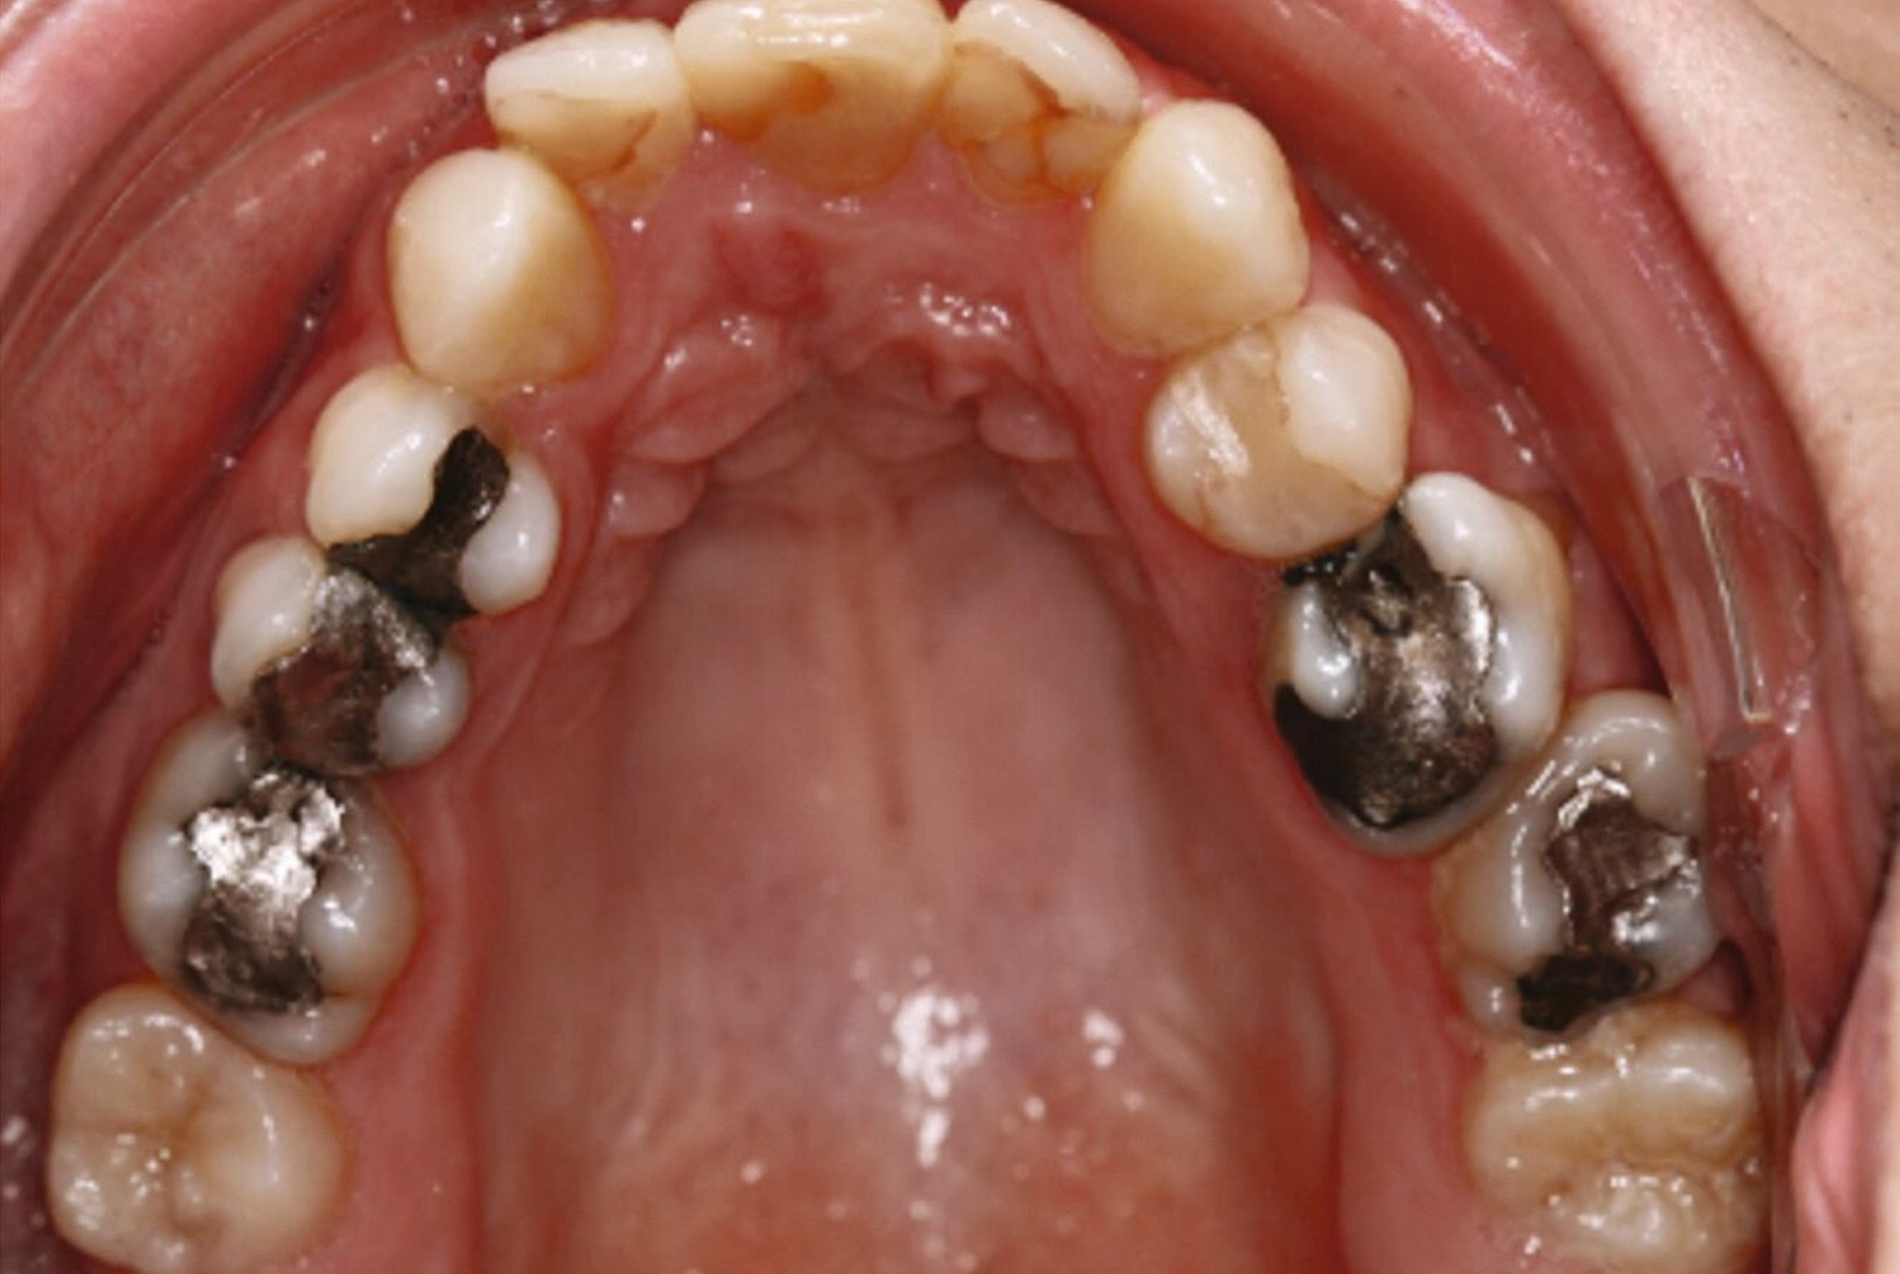

Aufgrund einer hohen Kariesanfälligkeit und einer klinisch floriden Parodontitis waren bereits mehrere Zähne des Patienten extrahiert worden, darunter 16, 11, 25, 38, 35, 45 und 46. Die mesiale Kippung und Aufwanderung der angrenzenden Zähne ließ vermuten, dass der Zahnverlust zeitlich weiter zurücklag. Aufgrund der reduzierten Langzeitprognose des Zahnes 11 entschieden wir uns gemeinsam mit dem Patienten für eine Ausgleichsextraktion des Frontzahns.

Außerdem wurde vor der kieferorthopädischen Intervention die Parodontitis vom Hauszahnarzt behandelt, so dass im Anschluss eine Multiband-Apparatur im Ober- und im Unterkiefer eingesetzt und die Zahnbögen nivelliert werden konnten. Dabei wurden die seitlichen Schneidezähne 12 und 22 anstelle der Zähne 11 und 21 lückig eingeordnet. Die Lücken in Regio 35 und 45 wurden für eine spätere Versorgung vorbereitet.